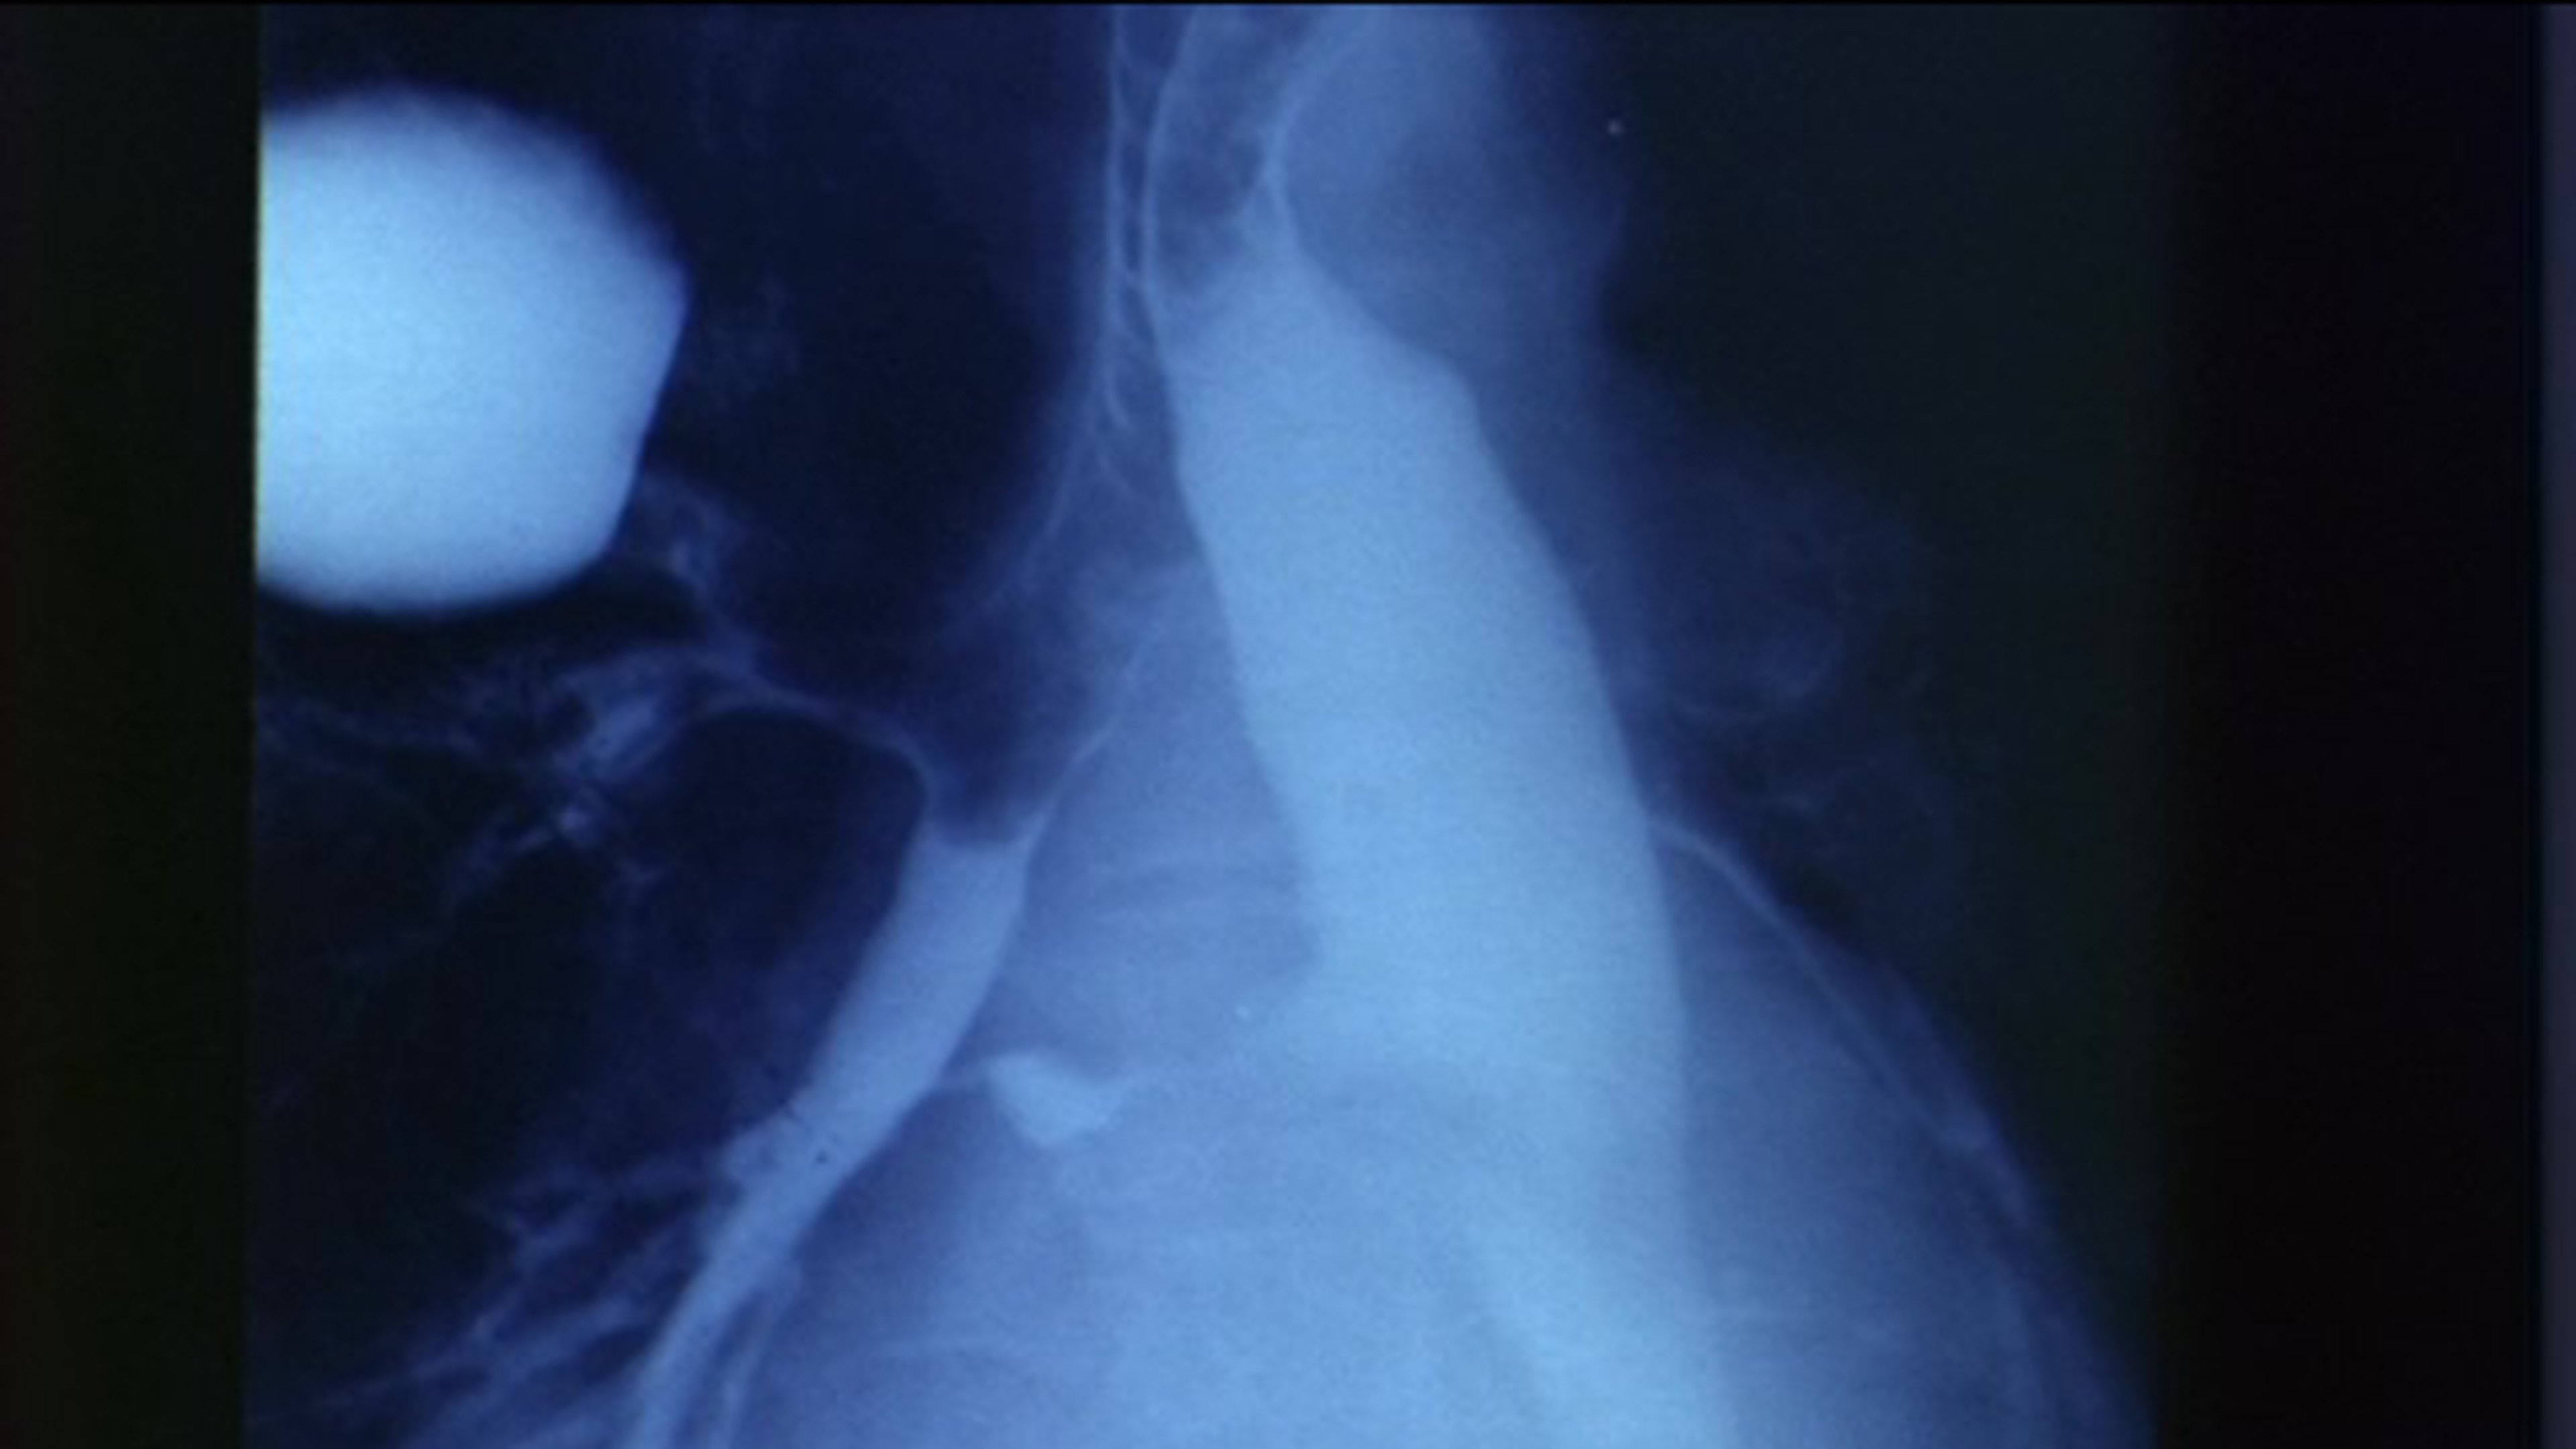

This is a film record of a surgical operation, performed in a Montréal hospital in December, 1968, to correct a rare congenital anomaly in a sixty-six-year-old male--a case in which there was a fistula between the normal oesophagus and a bronchial segment. A report of this case was published in the Canadian Medical Association Journal, May 9, 1970, v. 102.